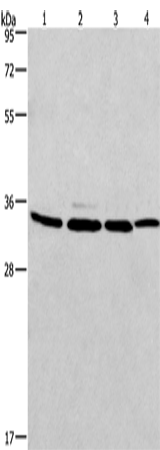

分类: 科研抗体货号: P07423别名: LRP, VAULT1应用: WB,IHC反应种属: Human, Mouse, Rat